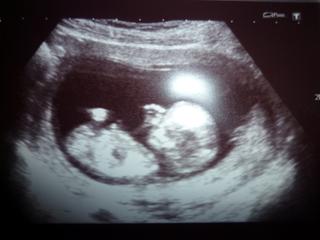

Ahojky tak sem byla na ty kontrolu sem dneska 8+3 a je vse v poradku uz mam i fotecku tak ji sem potom vlozim. Byl to krasnej pocit na kontrolu jdu az ve 12tydnu a to uz prej dostanu prukazku tak sem moc rada. Tak snad bude vse v poradku a preklenu zase ty 4tydny.

@zdeniii kráááásnáá fotečka.. gratuluju.. jéé, těším se, až bude mimi tak veliké.. já

Ahojky holky,tak mám za sebou konečně kontrolu.Mimi povyrostlo už sme 12 plus 6.Krásně sme kopaly nožičkama a i mi zamávalo 🙂 .Fotečku sem dodám.Tak se mi zase na pár dní ulevilo 🙂

krasny...taky mam fotecku na fotoblogu

Ahojky,děkuju🙂.Máš se na co těšit.Bylo to nádherný,jak bylo vidět,že kope,jak si tam krásně plave,rovnou mi udělala ten screening,tak řikala,že roštěp páteře nemá,že pěkně dovádí.Vůbec sem nemohla uvěřit,že to co je na tý obrazovce mám v bříšku,ptž to mám furt jen malinkatý.Jinak sem dnes ráno poprvé zvracela,ale doktorka řikala,že už by mělo být jen líp,tak doufám že bude